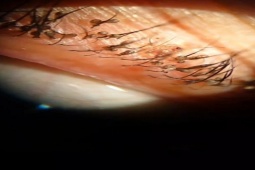

Người phụ nữ được thăm khám trong tình trạng quanh mí mắt bị ngứa, cộm, sưng đỏ và chảy nước mắt. Dưới kính hiển vi, các bác sĩ phát hiện bầy rận mu đang ký sinh trên mí mắt, đẻ trứng chi chít lên lông mi người bệnh.